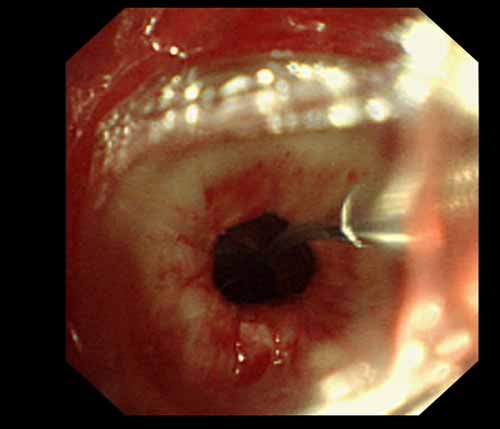

患者李某某,女,45歲,因氣管插管咳嗽、喘憋10天入院。頸部CT檢查示聲門(mén)下約20mm處氣管明顯狹窄,狹窄段長(zhǎng)約26mm,最窄處直徑約4.4mm。支氣管鏡檢查見(jiàn)聲門(mén)下約2cm氣管呈漏斗狀縮窄,直徑約4-5mm,支氣管鏡無(wú)法通過(guò)。經(jīng)科室討論,決定行電子支氣管鏡下氣管球囊擴(kuò)張治療。與患者及家屬充分溝通并經(jīng)三方見(jiàn)證談話簽署知情同意書(shū)后,在患者持續(xù)吸氧、局麻下,科主任于世倫主任醫(yī)師帶領(lǐng)治療小組為患者實(shí)行電子支氣管鏡下氣管球囊擴(kuò)張術(shù)。手術(shù)過(guò)程順利,出血量很少,術(shù)后患者呼吸困難癥狀即可明顯緩解。10天后行二次擴(kuò)張,患者日?;顒?dòng)無(wú)明顯喘憋,二次術(shù)后5天出院。

術(shù)前聲門(mén)下的漏斗樣狹窄口 術(shù)中球囊擴(kuò)張 術(shù)后擴(kuò)張開(kāi)的氣管管腔